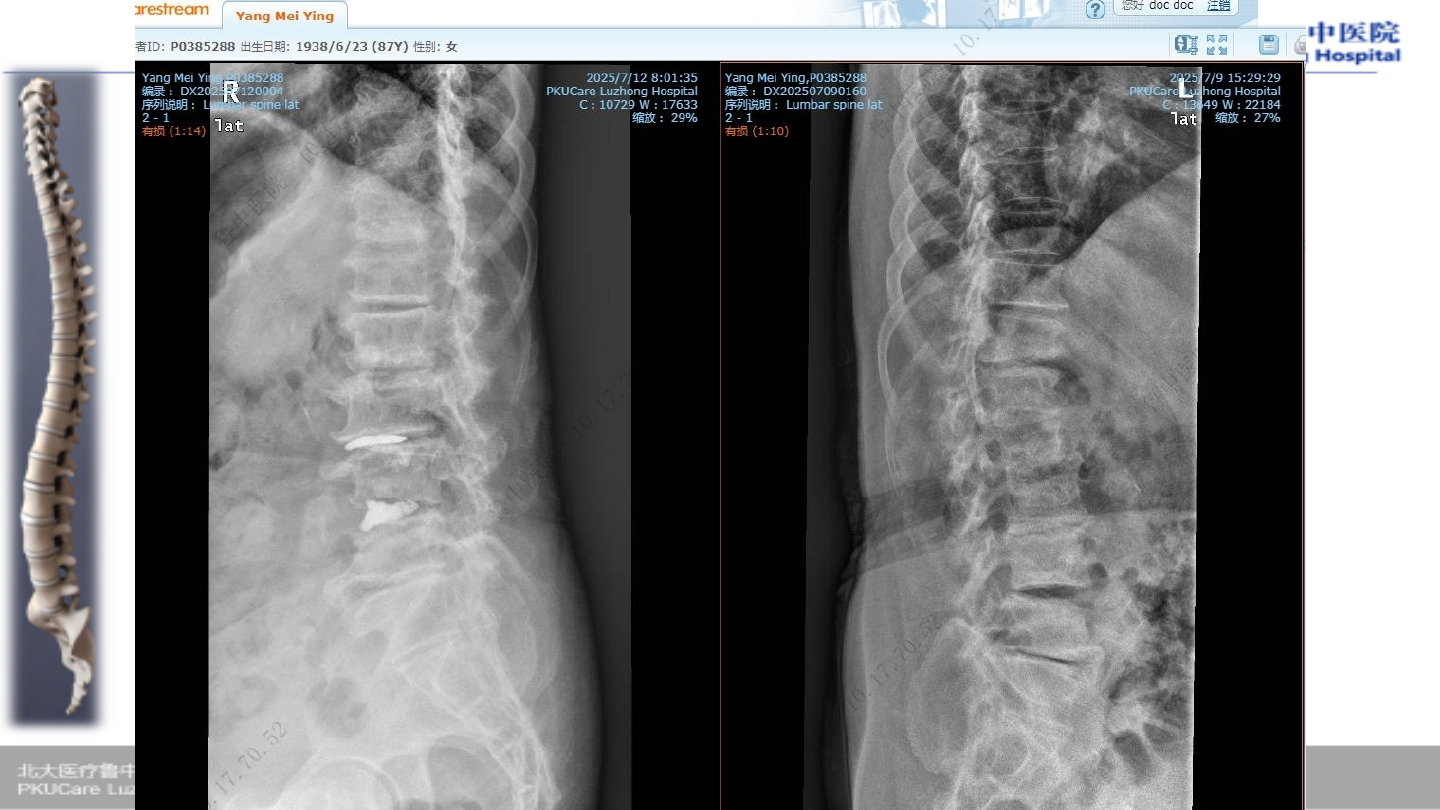

患者,杨某

,女性,

86

Ø

腰背部疼痛伴双下肢麻木疼痛

2

年,加重一周

腰背部疼

痛伴活动

受限

年前

症状加重

一周前

病例

3

查体

腰椎活动受限,腰段压痛及叩击痛

双下肢小退外侧、足背感觉减退

膝、踝反射存在、病理征阴性

VAS 8

血常规、血凝常规(阴性)

肝肾功能、心电图(阴性)

骨密度

T

值:

-3.9

术前

X-ray